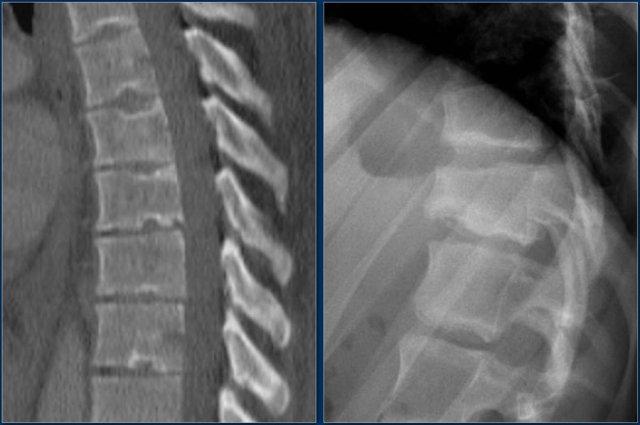

Các hình ảnh minh họa hai trường hợp viêm xương sụn.

Hình bên phải có kèm gù cột sống.